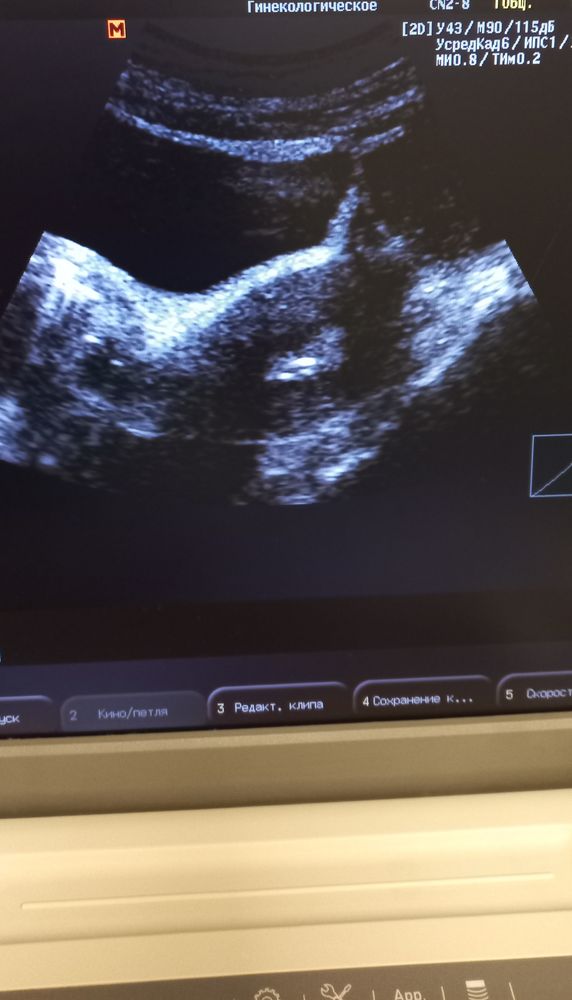

На фото маленькая точка- эмбрион, попросила быстренько сфоткать- на память🤩

Единственное, что сказали- из 13 клеток оплодотворились 7, переносим 1 отличника, остальные- в заморозку...